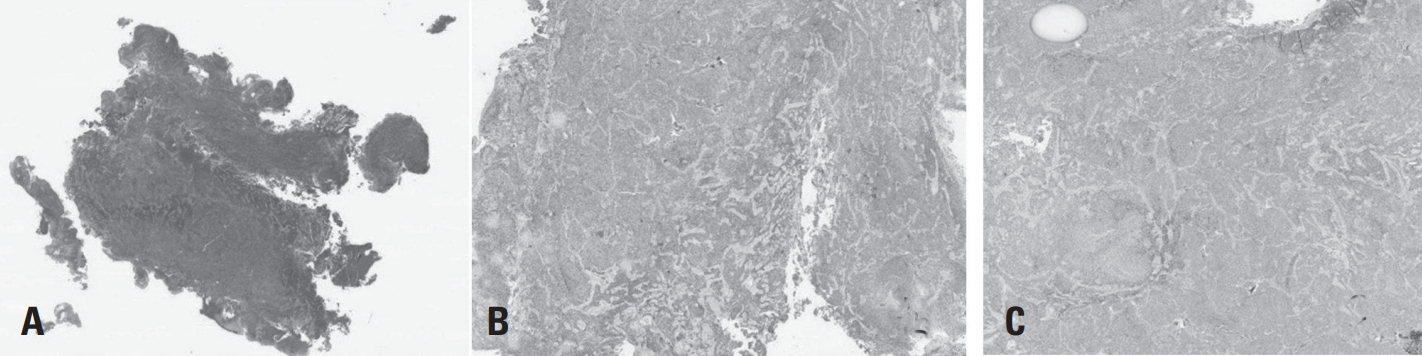

Histopathological examination revealed microvascular proliferation and necrosis on hematoxylin and eosin (H&E) staining. Immunohistochemical analysis confirmed a diagnosis of WHO grade IV glioblastoma, characterized by IDH wild-type status and absence of Histone H3 mutation (Fig. 3 A-C).

Fig. 3.

(A) Hematoxylin and eosin (H&E) staining shows microvascular proliferation and necrosis, consistent with high-grade glioma. (B) Immunohistochemistry for IDH-1 reveals wild-type expression. (C) Immunohistochemistry for Histone H3 shows no mutation, supporting the diagnosis of IDH-wildtype glioblastoma.

Fig. 3. (A) Hematoxylin and eosin (H&E) staining shows microvascular proliferation and necrosis, consistent with high-grade glioma. (B) Immunohistochemistry for IDH-1 reveals wild-type expression. (C) Immunohistochemistry for Histone H3 shows no mutation, supporting the diagnosis of IDH-wildtype glioblastoma.